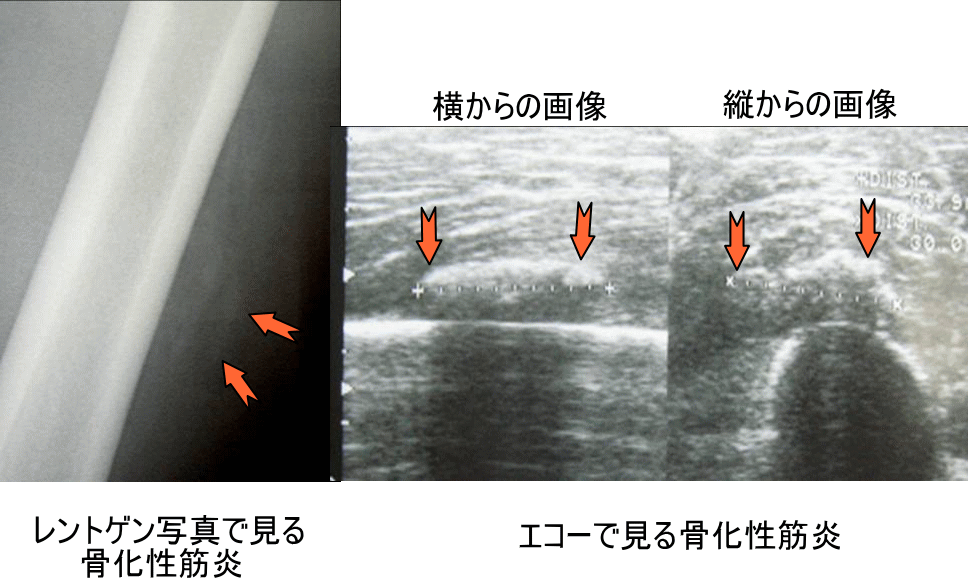

最初の損傷から 2 ~ 4 週間以内に、新しい骨の成長がX 線で確認できます。これは医師が最終診断を下すのに役立ちます。